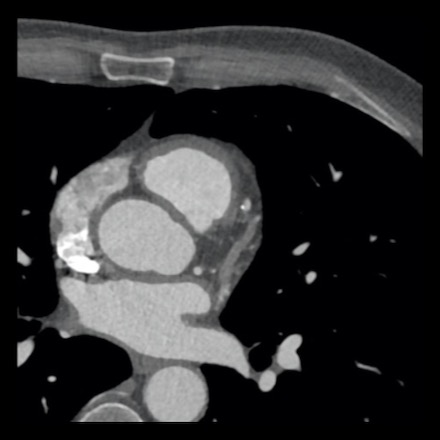

case 2 – CAD-RADS 5/P2/S

First, scroll through the CTA images.

How would you describe the findings on the coronary CTA?

The findings are:

- Stent in the mid

LAD with low-attenuation within the stent suggestive of minimal in-stent

restenosis (<25%). Non-calcified plaque distal to the stent

causing mild stenosis (25-49%). Notice bridging on a short segment in

the distal LAD. - Non-calcified

plaque in the LCX causing mild stenosis (25-49%). - Occlusion of the

proximal OM1 branch with distal filling. - Calcified and

non-calcified plaques in the proximal RCA causing mild (25-49%) stenosis. - Total plaque burden

is moderate based on SIS (four segments including proximal RCA, mid LAD, prox

LCX and OM1).

Due to the occlusion of OM1 branch and presence of the stent, this case

reads as CAD-RADS 5/P2/S, which means that this patient needs further

diagnostic workup.